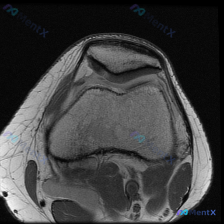

今天看到一个很有代表性的读片问题,整理出来和大家分享讨论。 病例基础信息 这是一张膝关节MRI T2序列轴位图像,临床提问是:图像中是否存在可识别的软骨异常? 影像阅片结果 先给大家整理一下这张图像的客观观察: 1. 解剖层面:髌股关节层面,显示髌骨、股骨滑车沟及周边软组织结构 2. 骨骼结构:髌骨...